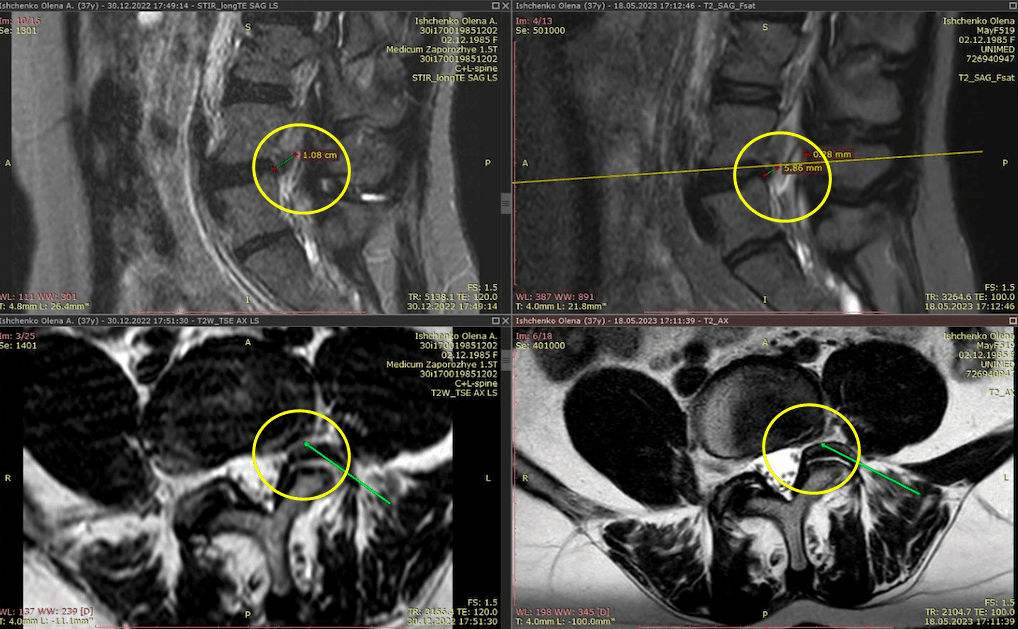

Метод лікування грижі шляхом стимуляції резорбції в Україні був впроваджений у 2020-2021 роках.  Алгоритм оцінки грижі на предмет резорбції, що використовується у клініках – є авторським, розроблений лікарем Боханом А.Ю.